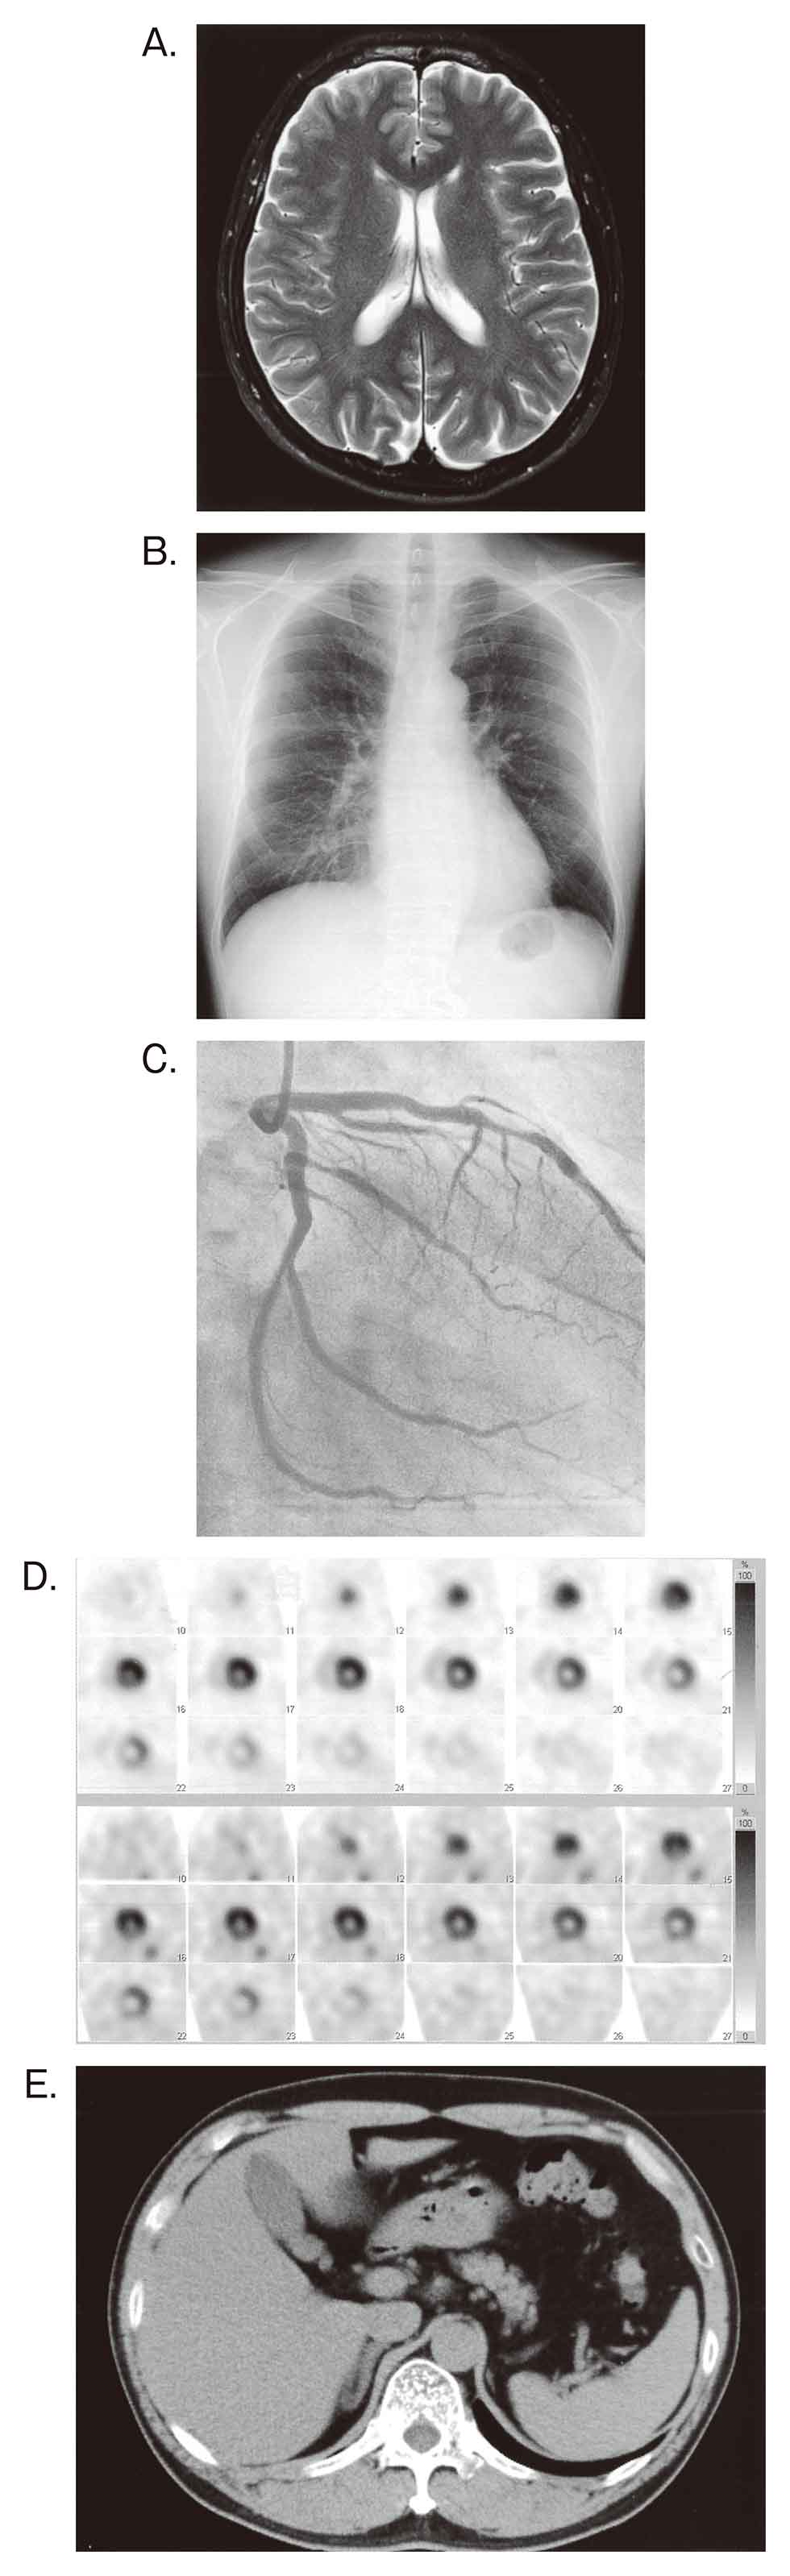

71ASbdgC9mL.jpg。第114回看護師国家試験 午前必修問題 | 一般財団法人厚生労働。2ページ目:第114回 看護師国家試験 解答速報 ただいま公開中。看護師国家試験2024年に使用していた国家試験対策のものです。・でた問 ¥1681・ここだけおぼける ¥1500+税・ゴロ勉 ¥1500+税・プチナース看護師国家試験過去問題集 ¥5940・クエスチョンバンク必修問題集 ¥3190・クエスチョンバンク国家試験問題解説 ¥6490・1番最新の国家試験で実際に私が解いた問題と添削した解答付きのもの(113回の国試問題)・その他問題集10冊プラスプリントは自分が模試を受けた解説に貰ったり、学校の授業で使用をしたものなので非売品ですが、解説がしっかり載っており非常に分かりやすく役に立ちました。これだけついてこの値段はかなりお得です。送料はこちらもちで配送はクロネコヤマトでします。。必修問題 – 114回看護師国家試験 – 心電図波形 心室脈拍。これさえやっていれば東進などの10万以上する高い講義に通っている方もいましたが、そういうものにお金を払わなくてもこれだけで私は250点以上は取れました。AGOS TOEFL 教材 2017年 CD8枚付き。メキメキ力がつく受験英語の集中講義。使用していたので安くしています。24年度卒 歯科衛生士教科書。KORON 警察 昇任試験 2024 1〜10。4月からは仕事で忙しくなるので3月中に購入いただけたらすぐにお送りできます。東進教材漢文。【25冊】ひろゆき 西村博之 全巻帯付き 2ちゃんねる 論破王 成田悠輔 ja。ご検討宜しくお願いします。希学園基礎計算問題集&難問計算問題集